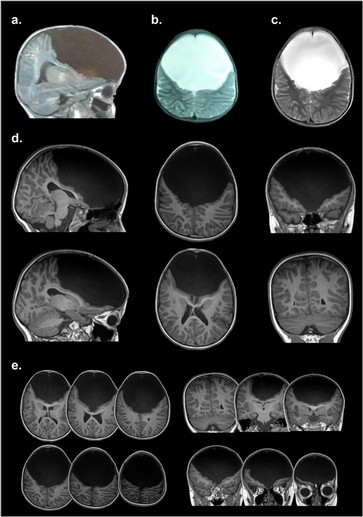

"Gabriela carece del lóbulo frontal, que es la parte más evolucionada que tiene el cerebro. Allí se determina el control de la conducta, el procesamiento de las emociones, los deseos, las llamadas ejecutivas de determinada acción, el lenguaje y otras más. Esa porción cerebral es realmente como una computadora compleja, donde se mantienen más conexiones. La niña presenta solamente un 10% de esa corteza prefrontal, pero al estudiarla vimos que no tiene ninguna conexión cerebral", sostuvo Ibañez.

Katherine decidió contactarse con los médicos argentinos que actualmente tratan a su hija ya que consideró que en Colombia la habían diagnosticado y tratado muy mal. Inclusive, los médicos colombianos pensaron que se trataba de un caso de hidrocefalia y la operaron para colocarle una válvula que drenara el líquido. Gabriela pasó varios días en terapia intensiva recuperándose de una operación que no sirvió de nada. Pero su fuerza de voluntad la ayudó a sobrellevar ese trauma.

Antes de viajar a conocerla, el doctor Ibañez vio las resonancias efectuadas en su cerebro y pensó que no caminaba, por carecer de corteza motora, o que no hablaba, porque le faltaba las áreas de Broca.

"Si bien las imágenes estructurales muestran la ausencia del lóbulo cerebral, la tractografía y conexiones de neuronas se reorganizaron de forma plástica desde su concepción en el seno materno y durante su niñez. También observamos que las conexiones funcionales, las redes por donde se transmiten las órdenes cerebrales se reorganizaron", aclaró el profesional.